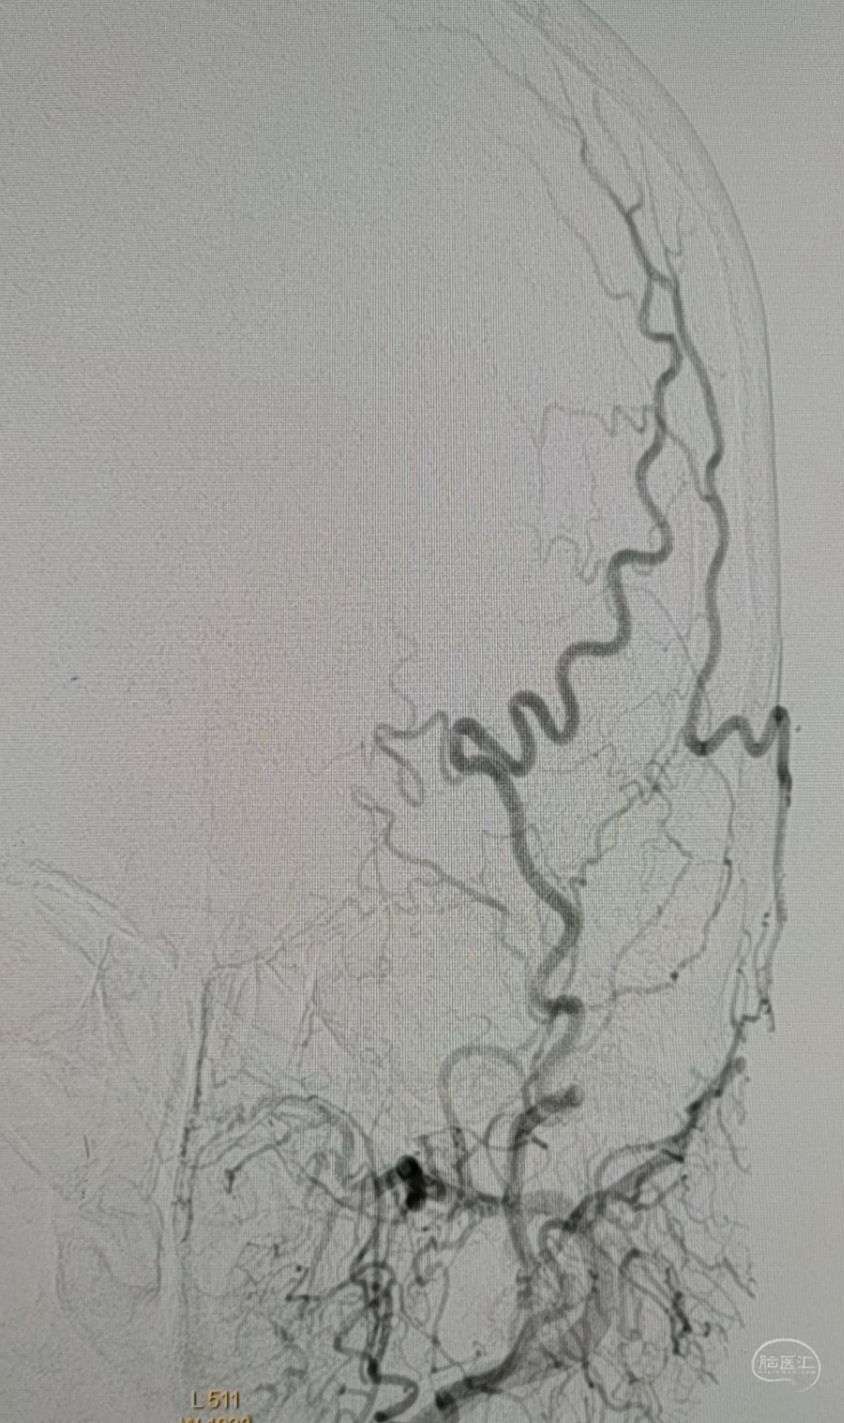

行颞浅动脉-M4端侧吻合。

吻合14针。

行颞浅动脉-M4端侧吻合。

颞浅A一只吻合,一只种植。吻合14针。

行颞浅动脉-M4端侧吻合。

吻合14针。

行颞浅动脉-M4端侧吻合。

吻合14针。

行颞浅动脉-M4端侧吻合。

吻合16针。